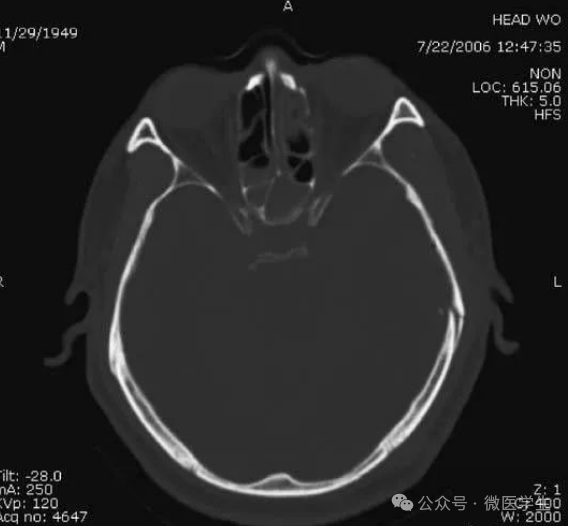

- 颅前窝底部:眼眶,眼球,筛窦,蝶窦,前床突等。

- 颅后窝:前缘—岩骨;后缘—枕骨;鞍背后方—脑桥前池,向两侧延伸为脑桥小脑角池。

- 第四脑室:位于颅后窝中线上,后面紧邻小脑蚓部,其两侧为小脑扁桃体。

- 延髓、脑桥:位于第四脑室前。